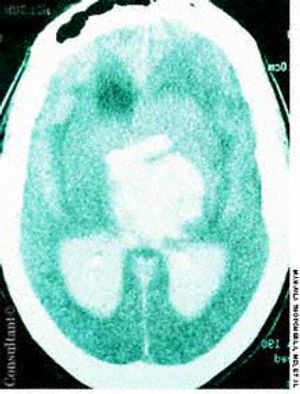

A 60-year-old comatose man was brought to the emergency department (ED). He had a history of diabetes, hypertension, and alcohol abuse. Relatives reported that the patient was noncompliant with his antihypertensive medication regimen.